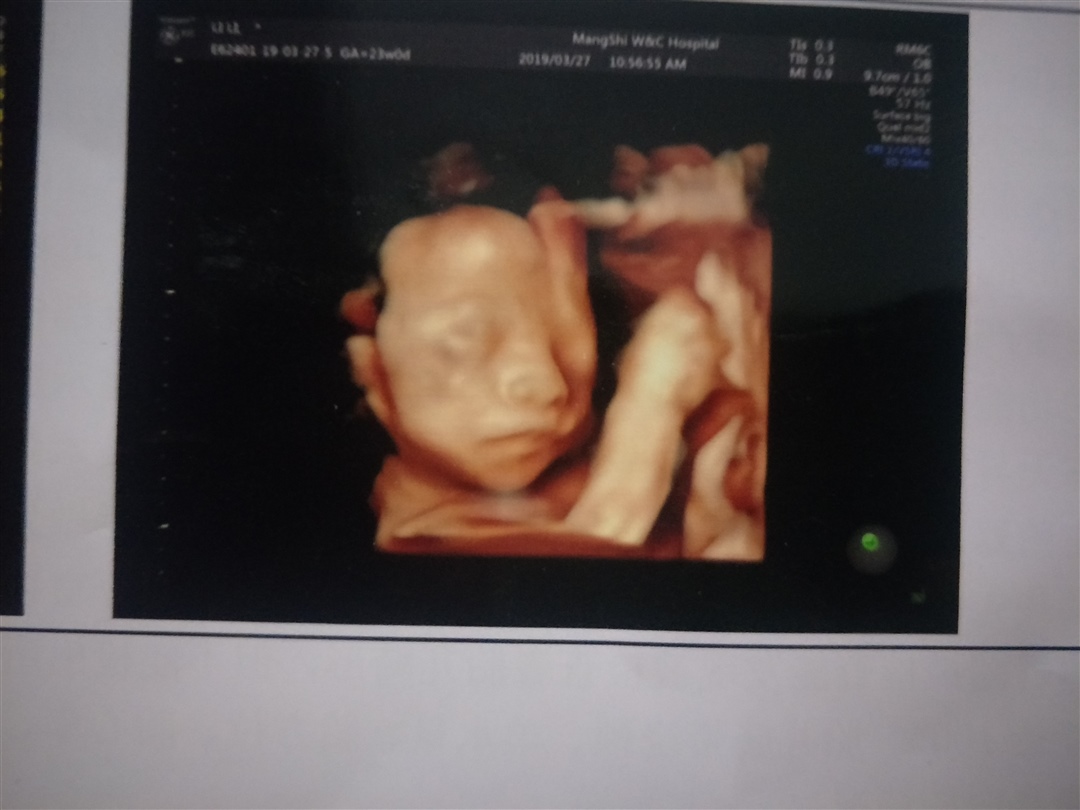

孕24周+4天